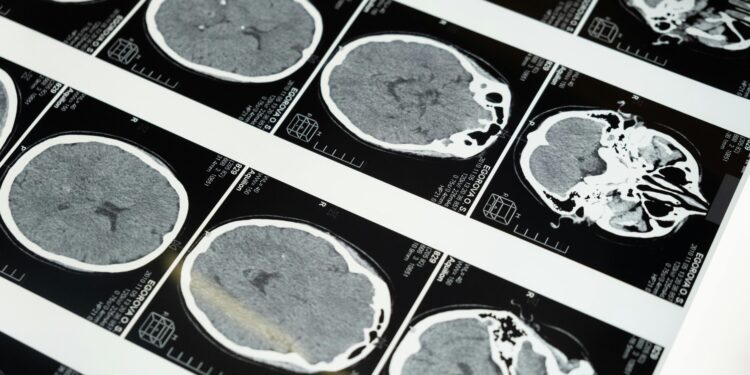

Em experimentos, camundongos expostos ao PM2.5 por 10 meses apresentaram sintomas alarmantes. Observou-se uma atrofia significativa no lobo temporal medial, crucial para a memória, e um aumento no acúmulo de proteínas relacionadas à neurodegeneração.

Esses achados sugerem que essas partículas aceleram tanto o aparecimento quanto a progressão de doenças neurodegenerativas em organismos predispostos.